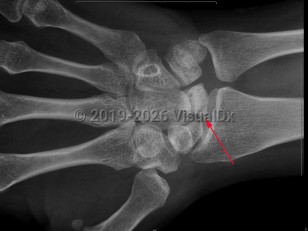

Avascular necrosis (osteonecrosis) is characterized by tissue death due to reduction or loss of blood supply to a bone. Causes include joint or bone trauma, fatty deposits in blood vessels, corticosteroid use, alcohol abuse, and some diseases. Other risk factors are chemotherapy, radiation therapy, and organ transplantation. May occur at any age, but most commonly occurs in adults aged 30-60. Patients are typically asymptomatic early on, but most experience joint pain increasing in severity as the disease develops. The femoral head site is most commonly affected, but the humeral head site, femoral condyles, and small bones are also sites of common occurrence. Typically, clinical presentation consists of sudden onset of pain in the joint.

Related topics: avascular necrosis of knee, avascular necrosis of scaphoid, Köhler disease, osteonecrosis of the femoral heads, osteonecrosis of the humeral heads, progressive avascular necrosis of lunate